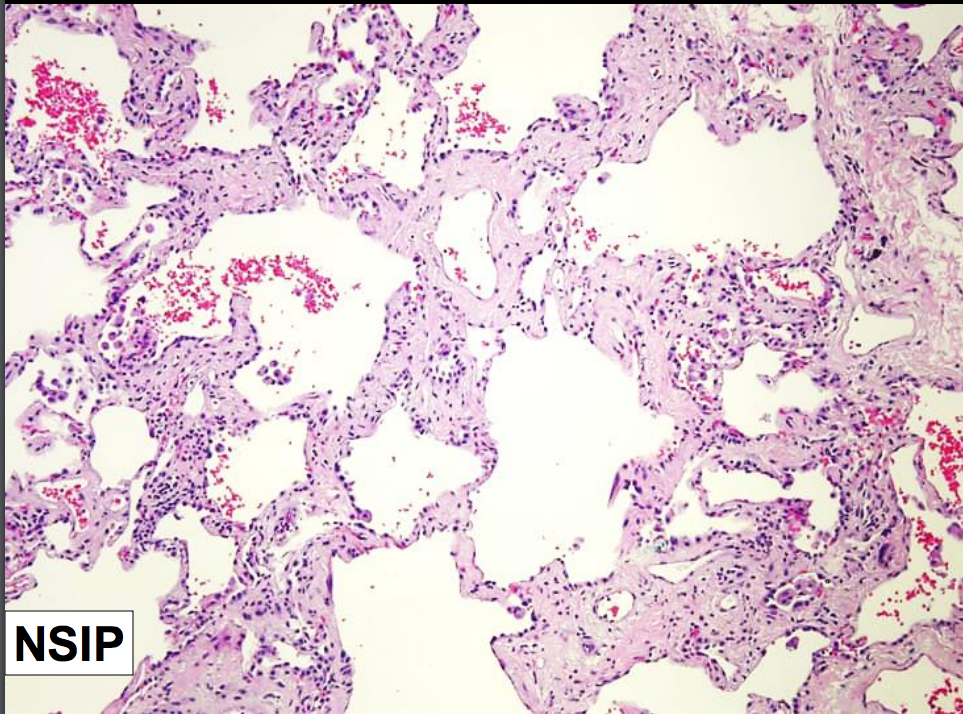

Nonspecific Interstitial Pneumonia

Nonspecific interstitial pneumonia (NSIP) is a chronic fibrosing interstitial lung disease that lacks characteristics of the other wellcharacterized (specific) diseases. It can be idiopathic, or may occur in the setting of an underlying connective tissue disease.

Characteristics of NSIP